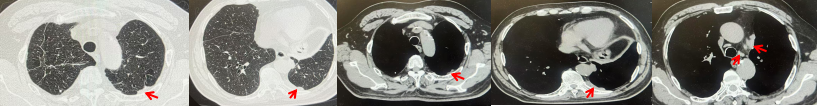

2024.11.19患者出现右侧胸痛,复查胸部CT检查示右侧胸膜肿物,大小约31mmX24mm,右侧4、5肋骨骨质破坏,考虑转移(如图2)。建议患者穿刺活检取病理明确诊断,患者拒绝,经MDT会诊后结合影像学表现及病史考虑为胸膜转移,肋骨转移,分期为rT0N0M1a IVA期,DFS仅仅17个月。2024.12.05起行信迪利单抗联合培美曲塞+卡铂方案治疗4周期,复查胸CT评效PR(如图3)。之后给予信迪利单抗+培美曲塞维持治疗6周期,期间复查CT评效PR(如图3)。目前信迪利单抗+培美曲塞维持治疗中,截止至目前PFS约为8个月,治疗期间未出现明显毒副反应。

图1:患者手术前(2023.06)胸部CT肺窗及纵隔窗

图2:患者胸膜及肋骨转移(2024.11)胸部CT肺窗、纵隔窗及骨窗

图3:患者免疫联合化疗治疗后胸部CT,(A、B)图展示信迪利单抗联合培美曲塞+卡铂治疗

4周期(2025.02)疗效,(C、D)图展示信迪利单抗+培美曲塞维持治疗6周期(2025.07)疗效